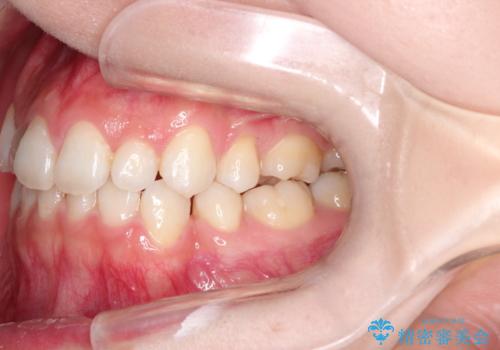

前歯の後戻りを部分矯正で整った歯並びへ

- 矯正治療後の上の前歯の後戻りを気にされて来院されました。

上の前歯のみにブラケットをつけて矯正治療を行いました。

部分矯正は、わずかなガタつき、ずれには有効的です。